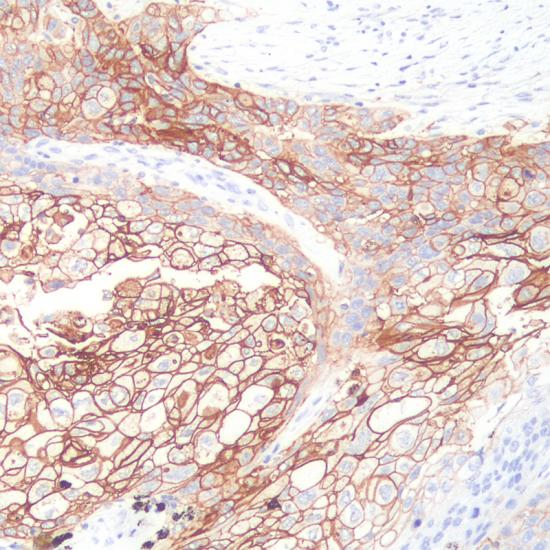

兔抗人PD-L1單克隆抗體

• 陽(yáng)性部位:

細(xì)胞膜

• 陽(yáng)性對(duì)照:

肺癌

PD-L1與其在T細(xì)胞上的受體PD-1相互作用,在免疫應(yīng)答的負(fù)性調(diào)控方面發(fā)揮重要的作用,該分子具有廣泛的組織表達(dá)譜,在一些腫瘤細(xì)胞中亦有較高的表達(dá),如乳腺癌、肺癌、腎癌、腸癌、食道癌、卵巢癌、宮頸癌、胰腺癌、黑色素瘤、神經(jīng)膠質(zhì)瘤等,與腫瘤的免疫逃逸機(jī)制相關(guān)。主要用于腫瘤治療的研究。